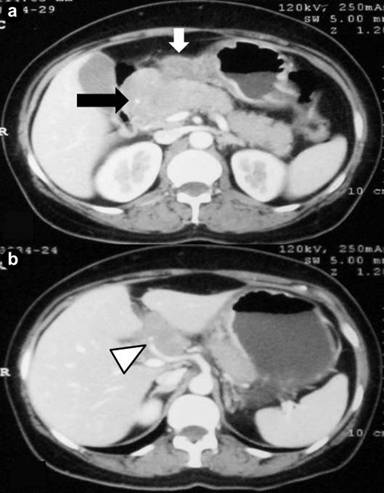

After initial stabilization with analgesics, hydration and parenteral nutritional support, a CECT abdomen was done for better characterization of pancreatic head mass. It revealed a 6x5 cm conglomerated lymph node mass in the peripancreatic and periportal region encasing the hepatic artery with preservation of fat plane between the mass and pancreatic head. There was circumferential wall thickening of body and antrum of stomach (14 mm) with luminal narrowing (Figure 1). CA 19-9 was normal. Upper gastrointestinal endoscopy showed thickened folds in the body of stomach with antral nodularity and a few superficial ulcers. First part of duodenum showed a 2x1 cm ulcer on the postero-superior wall (Figure 2).

Figure 1. Contrast CT abdomen showing (a.) thickening of gastric body and antrum (white block arrow) along with conglomerated lymph node mass in the peripancreatic region (black block arrow) with clear fat plane between the mass and pancreatic head and (b.) hepatic artery encasement (white arrow head). |